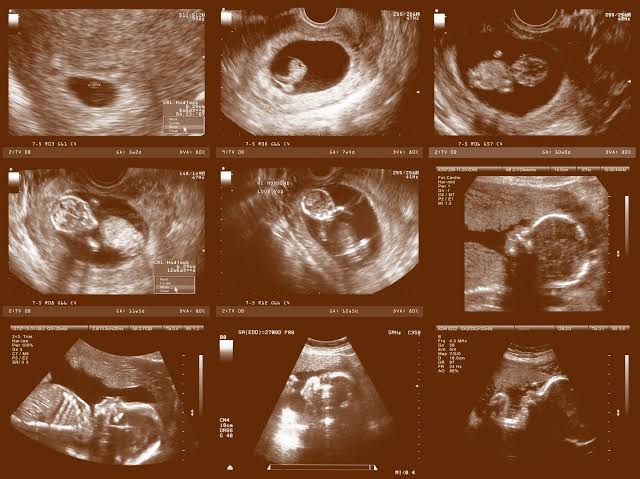

आश्चर्य है। तब तो अल्टा् साउंड वगैरह भी नहीं थे। हजारों साल पहले कैसे जान गये मनीषी?

डाक्टर अब कहते हैं कि गर्भस्थ शिशु का विकास ऐसे ही होता है।

एक ही दिन रक्त- रज मिश्रित शक्र का कलिल हो जाता है और पांच रात्रियों में कलिल बुदबुद बन जाता है। महीने भर में वह मांस का रूप धारण करता है और फिर गर्दन, सिर, कंधे, पीठ और पेट - इन पांच भागों में विभाजित हो जाता है।

वैसे ही हाथ ,पैर बगल, कमर आदि अंग हो जाते हैं। दो महीने में अंगों की संधियां उत्पन्न हो जाती हैं।

तीन महीनों में सभी शाखा- प्रशाखाओं की संधियां उत्पन्न हो जाती हैं और चार महीनों अंगुली आदि अवयव हो जाते हैं।

पांच महीनों में मुख, नाक, कान हो जाते हैं और दंतावलि, जीभ , नाखून आदि भी हो जाते हैं। छह महीनों में दोनों कानों दिद्र हो जाते हैं और उपस्थ व जननांग भी हो जाते हैं। सात महीनों में सिर के बाल आदि अंग-प्रत्यंग सम्पूर्ण हो जाते हैं।

आठवें महीने में स्पष्ट विभाजित हुए अंगों वाला हो जाता और पंच महाभूतों से युक्त परिपक्व होकर तैयार हो जाता है।